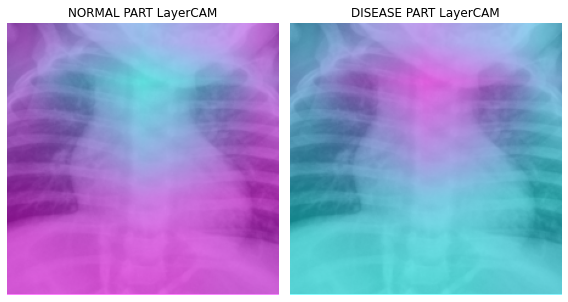

fig, (ax1,ax2) = plt.subplots(1,2)

dls.train.decode((x,))[0].squeeze().show(ax=ax1)

ax1.imshow(-cam_layercam.squeeze(),alpha=0.5,extent=(0,224,224,0),interpolation='bilinear',cmap='cool')

ax1.set_title("NORMAL PART LayerCAM")

#

dls.train.decode((x,))[0].squeeze().show(ax=ax2)

ax2.imshow(cam_layercam.squeeze(),alpha=0.5,extent=(0,224,224,0),interpolation='bilinear',cmap='cool')

ax2.set_title("DISEASE PART LayerCAM")

fig.set_figwidth(8)

fig.set_figheight(8)

fig.tight_layout()